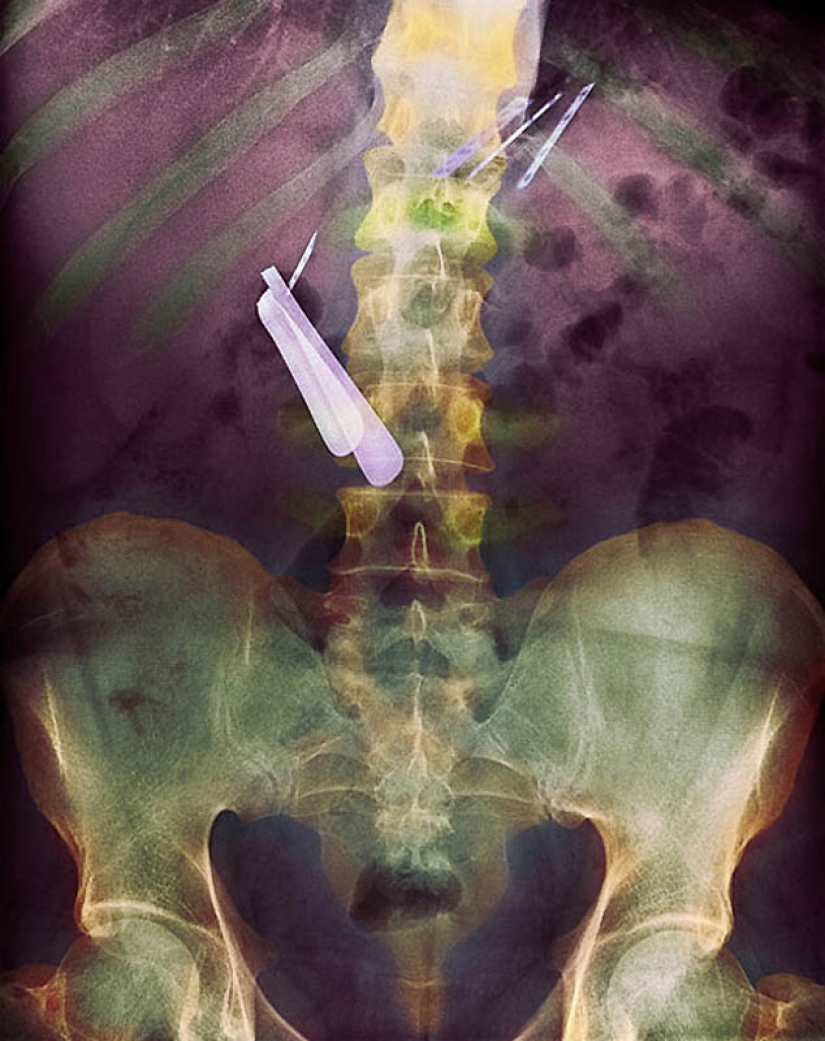

5. Color the objects that are swallowed by the patient, and stuck in his gut, including the spoon and the blade.